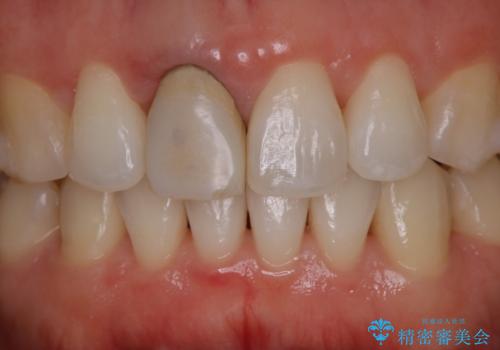

前歯の色が気になる オールセラミッククラウン(SP)

- 仮歯で矯正治療を行い、治療終了したためセラミックにて最後仕上がりをきれいにされたいという患者様の症例です。

矯正の時使用していた仮歯を新調し、その後最終的な形を作ってから型取りを行います。

色もきれいだと患者様も満足されておりました。